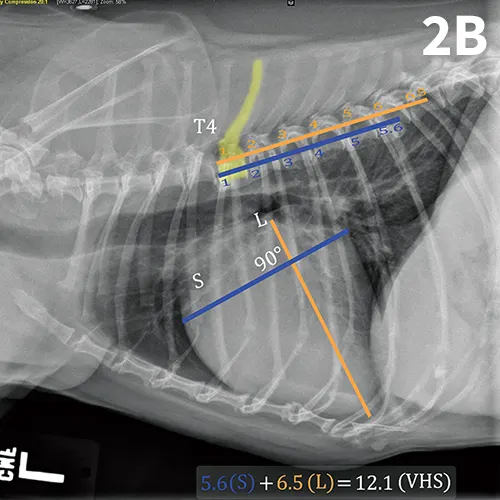

The ACVIM consensus statement on degenerative MVD recommends baseline thoracic radiography for dogs with a new murmur, then annually thereafter.6 For practitioners adhering to these guidelines, annual calculation of VHS and rate of change from previous imaging should become standard practice and may help identify those patients at higher risk of developing CHF in the coming year. Figure 2 illustrates annual radiographs taken in a patient with progressive cardiomegaly.

FIGURE 2A

Progressive cardiomegaly noted on annual evaluations in a dog with MVD.